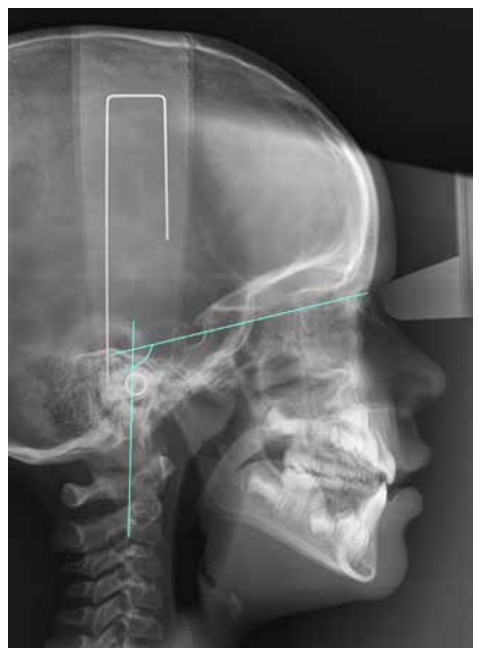

Características de la posición craneocervical con diferentes oclusiones en pacientes en desarrollo. Relación craneocervical y oclusión

En la actualidad la relación entre oclusión y posturología despierta un gran interés científico, sobre todo de cara a la instauración de un tratamiento multidisciplinar. Sin embargo, la diversidad de estudios se refiere sobre todo a la población adulta y no hay un consenso común entre las diferentes investigaciones. En base a ello nos planteamos como objetivo estudiar la posición craneocervical en diferentes oclusiones en población en desarrollo. Mediante un diseño de carácter transversal fueron seleccionados 64 pacientes pediátricos con historia clínica completa y radiografías laterales de cráneo de calidad. Las variables analizadas mediante el software de ImageJ® y Nemoceph® fueron FP-MP, ángulo ANB, OPT-SN, CVT-SN y Ad1-Ba. El análisis estadístico descriptivo y comparativo se llevó a cabo mediante el programa programa IBM SPSS® hallando posteriormente la fiabilidad intraexaminador. Los valores p obtenidos para cada una de las variables fueron 0,846 para FP-MP, 0,008 para el ángulo ANB, 0,155 para OPT-SN, 0,415 para CVT-SN y 0,221 para Ad1-Ba. Por todo ello, creemos que la posición craneofacial en las diferentes oclusiones podría estar determinada por el hecho de que el desarrollo todavía no ha finalizado.

Craniocervical position characteristics for different occlusions in developing patients: Craniocervical relationship and occlusion

Currently, the relationship between occlusion and posture arouses great scientific interest, especially during the establishment of a multidisciplinary treatment. However, the diversity of studies refers mostly to the adult population and there is no common agreement among the different investigations. Based on this, we aimed to study the craniocervical position in different occlusions in the developing pediatric population. Through a crosssectional design, 64 pediatric patients with complete clinical history and highquality lateral skull radiographs were selected. The variables analyzed by ImageJ™ and Nemoceph™ software’s were FP-MP, ANB angle, OPT-SN, CVT-SN and Ad1-Ba. Descriptive and comparative statistical analysis were carried out with IBM SPSS Statistics™ software, subsequently finding intra-examiner agreement. P-values obtained for each of these variables were 0.846 for FP-MP, 0.008 for ANB angle, 0.155 for OPT-SN, 0.415 for CVT-SN, and 0.221 for CVT-SN. Based on these results, we believe that the craniofacial position in the different occlusions could be determined by the fact that the development has not yet been completed.